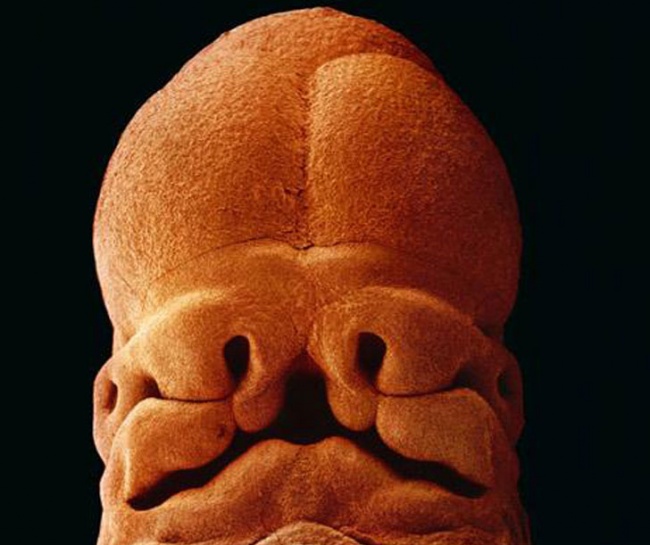

13 8-week-old embryo. The fetus is well protected in the fetal sac

14 10 weeks. Its eyelids are already half open

15 After 16 weeks